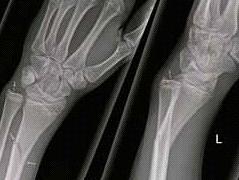

Fracturen Lees meer over Fracturen Fracturen

Jaarlijks melden zich bij de huisartsenpost en de Spoedeisende Hulp duizenden mensen met klachten van het bewegingsapparaat. Deze worden vaak veroorzaakt door een trauma. De oudere patiënt die valt, de sporter die een trap heeft gehad van een tegenstander. In dit artikel wordt onder andere aandacht besteed aan de anatomie van het botweefsel, soorten fracturen, symptomen van fracturen en de behandeling.